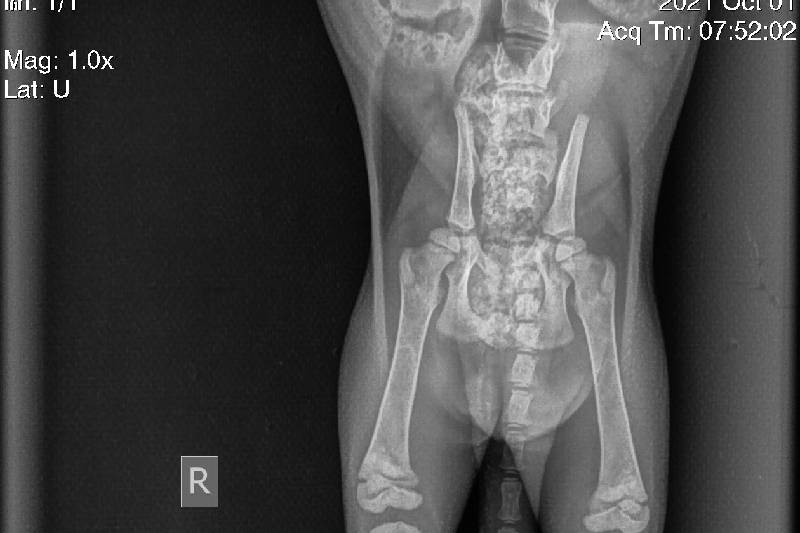

We rescued Marcie, a 2 month old kitten, 3 weeks ago from a construction site. Since then she has had two toes amputated, and an x-ray that shows only one of the fractures in her spine, and a tail amputation. Her life isn't at immediate risk and her condition is stable at the moment, but we still have no idea what kind of damage happened to her spine and we want to get her to a neurologist to see if she needs any more surgeries done. As of right now, we have enough money in donations to pay for a neurologist visit to get more x-rays done, a MRI scan, and a diagnosis/plan of treatment. However, we are unable to find a charity that we can be approved for yet so if the neurologist decides she needs surgery on her spine then we won't have many options left. We have opened donations again for the time being, but we won't have any answers as far as plans of treatment or costs until her Neurologist visit on the 20th. We will keep you updated as much as possible until then.